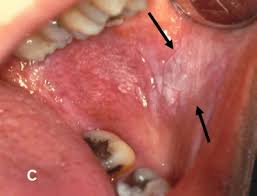

- Leukoplakia: White patches in the mouth

- Oral lichen planus: A potentially malignant disorder that can appear in different subtypes